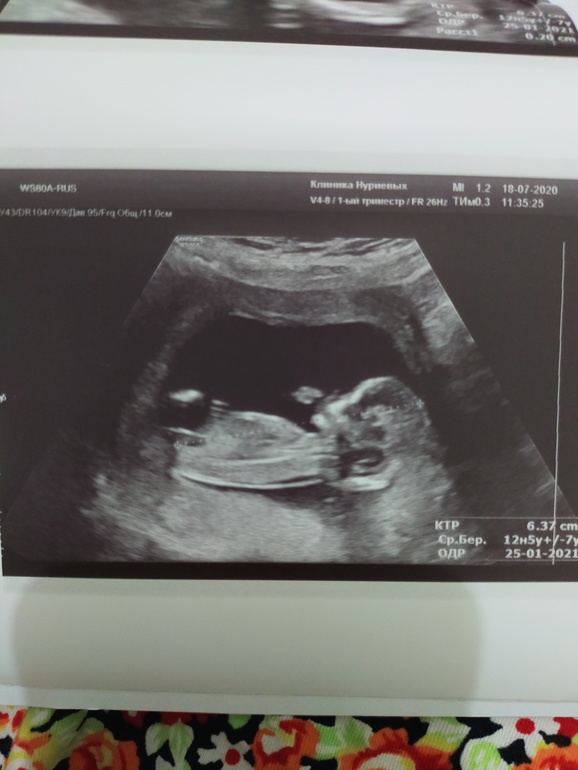

На узи зашли с мужем. Наконец-то и он увидел малыша))) Сначала он лежал не очень удобно для замеров, но когда врач сказала нужно чтобы повернулся, малыш сразу повернулся как надо)))

Ребеночек наш развивается отлично, ттт 🙏

Воротничковые зоны, носовая кость все в норме. Кровоток в норме. Ктр 63 мм. Чсс 157 ударов.

Плацента по передней стенке, как и говорили ранее. Правда низкое предлежание. Порадовала шейка: 45 мм. 3 недели назад была 37 мм.

Предположили девочку, я почему-то думала что скажут мальчик)))) посмотрим на следующем узи)))